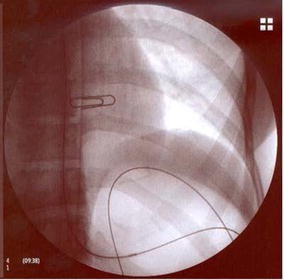

Fig. 1

Fig. 2

Fig. 3

1. The inability to properly place a guidewire for safe dilatation was defined when a loop of the distal end of the guidewire was unable to be formed within the stomach before dilatation was initiated.

2. Complete luminal stricture was defined when there was an inability to identify a luminal orifice to negotiate a guidewire.